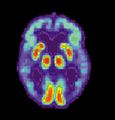

مرض ألزايمر هو مرض تنكسي وقاتل يصيب المخ، حيث تُفقد الاتصالات الخلوية بخلايا المخ. يعتبر مرض ألزايمر من أكثر أنواع الخرف شيوعاً.[2] عالمياً، يصاب بمرض ألزايمر حوالي 1-5% من السكان.[3] تقع النساء بشكل غير متناسب ضحايا لمرض ألزايمر، مع وجود أدلة تشير إلى أن النساء المصابات بمرض ألزايمر يظهرن ضعفاً إدراكياً أكثر حدة مقارنة بالذكور المصابين بالمرض، بالإضافة إلى معدل أسرع من التدهور السلوكي.[4]

مسح PET لمخ غير مصاب - الصورة مقدمة من مركز الإحالة والتوعية بمرض ألزايمر التابع للمعهد الوطني للشيخوخة بالولايات المتحدة.

مسح PET لمخ مصاب بمرض ألزايمر - الصورة مقدمة من مركز الإحالة والتوعية بمرض ألزايمر التابع للمعهد الوطني للشيخوخة بالولايات المتحدة.